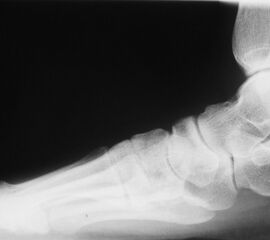

Röntgenaufnahme des Fußes (unter Belastung) in dorsoplantarem, seitlichen und schrägem Strahlengang (Abb. 1a-c).

Beurteilung des ersten Intermetatarsalwinkels (IMA), des Hallux valgus Winkels (HVA), des distalen (Distal Metatarsal Articular Angle, DMAA) und proximalen Gelenkflächenwinkels der Grundphalanx (Proximal Phalangeal Articular Angle, PPAA). Möglicherweise muss die Arthrodese des TMT-1-Gelenks mit weiteren distalen Eingriffen zur Korrektur des Gelenkwinkels kombiniert werden (z.B.: retrokapitale Osteotomie oder Grundphalanxosteotomie).

Zur Vollansicht bitte die Bilder anklicken.

Abbildung 1a

Abbildung 1b

Abbildung 1c